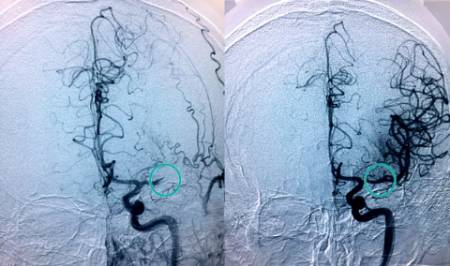

"Cuando una arteria del cerebro se obstruye se dispone de una ventana de muy poco tiempo para recanalizarla", explica el doctor Jaime González Valcárcel, neurólogo coordinador de la Unidad de Ictus del Complejo Hospitalario Ruber Juan Bravo. "Cada minuto cuenta en la fase aguda del ictus. Sabemos que por cada 15 minutos que se adelanta la primera intervención en caso de ictus disminuye un 4 por ciento el riesgo de discapacidad y también en un 4 por ciento la mortalidad".

La Unidad de Ictus de Quirónsalud en Madrid dispone de un sistema de telemedicina, denominado Teleictus, que permite que un neurólogo pueda ver durante las 24 horas del día a cualquier paciente con sospecha de ictus del Complejo Hospitalario Ruber Juan Bravo, Hospital Universitario Quirónsalud Madrid

; Hospital la Luz

y Hospital Quirónsalud Sur

. "El neurólogo de guardia del Complejo Hospitalario Ruber Juan Bravo puede acceder en tiempo real a la exploración del paciente y a sus pruebas del resto de centros, pudiendo ser tratado el paciente en un primer momento o trasladarlo para ser intervenido y extraer el trombo si fuera necesario", detalla el doctor Rafael Arroyo.